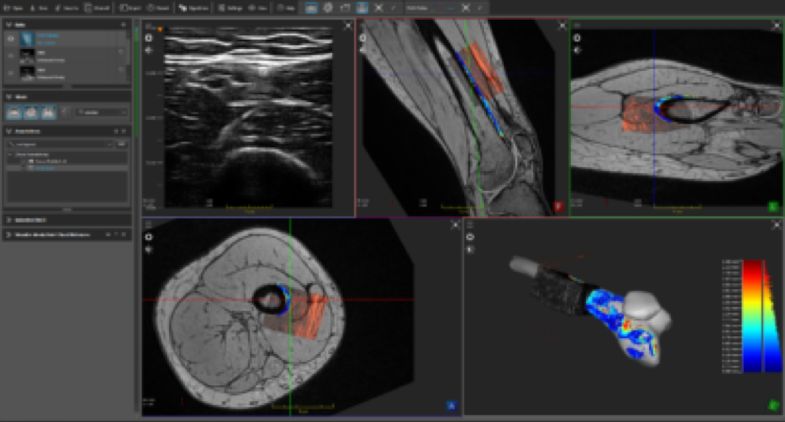

英伟达旗下孵化的一家初创企业ImFusion则独辟蹊径,借助AI影像生成技术,开创了从二维平面超声影像生成三维立体模型的新方法。他们以对应病人的二维超声影像和三维CT影像作为训练数据,让AI找到二维和三维影像之间的潜在联系,从而帮助医生更好地理解、感知病人体内的状况。

(将2D超声影像转化为3D人体模型,图片来自英伟达)